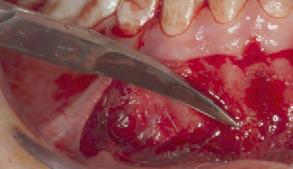

Estudios tomográficos en los cuales se observa tumoración expansiva a piso nasal de 3 centímetros de diá metro aproximadamente isodensa a tejidos blandos en zona de pala dar blando (Figura 3A y 3B). Motivo por el cual se decidió realizar biopsia incisional (Figura 4A , 4B y 4C) obte niendo un diagnóstico de Adenocar cinoma de células basales en paladar blando (Figura 5) con el cual se rea lizó referencia al centro oncológico naval para su seguimiento y trata miento. Actualmente se encuentra en tratamiento de quimioterapia.

Figura 4. A. Marcaje con bisturí de la muestra a tomar. B. Lecho quirúrgico de la muestra tomada. C. Afronte de la herida. A B C